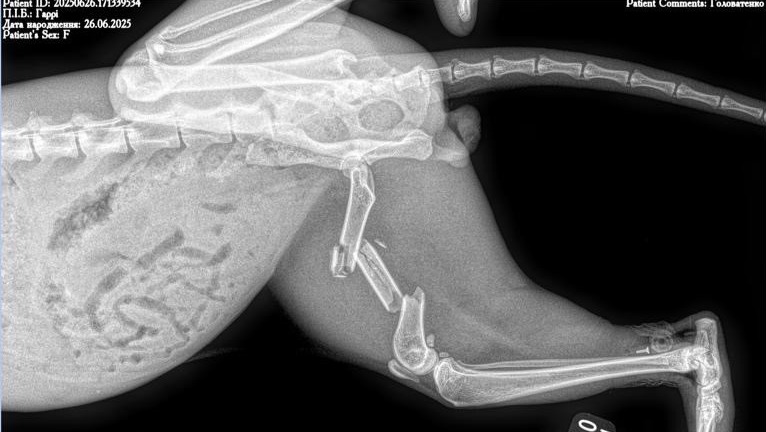

Then one day, Gary suddenly appeared dragging a completely shattered leg behind him - and then disappeared again. We tried to find him day in and day out, and when we did, he was so weak that crows were circling around him. We assume that Gary was hit by a car, which left him with multiple fractures.

In June, Gary underwent major surgery at VetFamily veterinary clinic to repair his injury, which the vets described as horrific. His leg was stabilized with external fixators, and he remained in in-patient care at Cat+Vet clinic for two months. Recently, we were able to move him into foster care so he could continue recovering in a calmer environment.

During his first week in foster, it became clear that something had gone wrong with the fixators. We rushed him to ArtVet clinic, where it was confirmed that the fixators had failed and had to be removed. Gary underwent another emergency surgery and is now recovering in a small crate to limit his movement as much as possible. At this stage, we still don’t know whether he will be able to keep his leg, but we are doing everything we can to support his recovery and ensure he receives the best care possible.

To give a clear picture of his injury and current condition, we’ve included two videos at the end. Please note that while there is no blood or gore, the first video shows his broken leg and the second shows the fixators, which some may find disturbing.